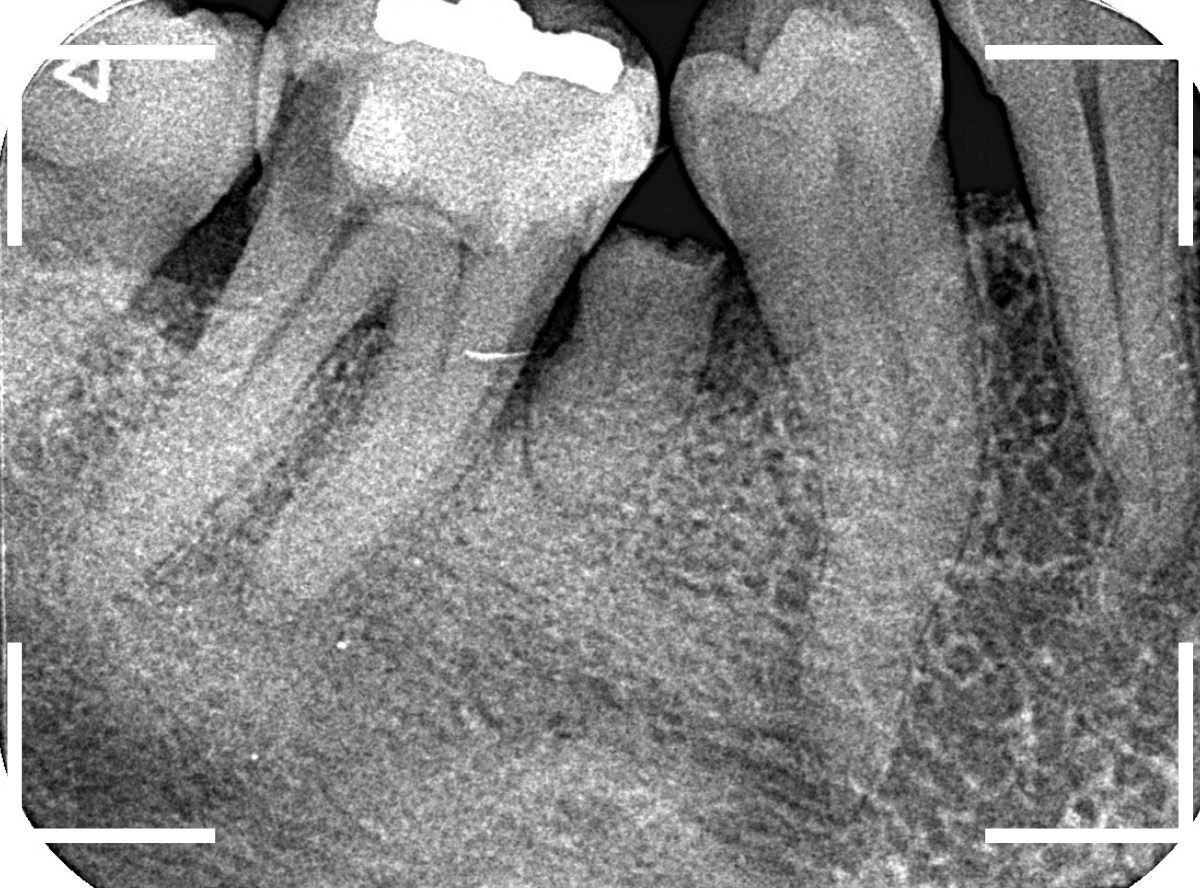

レントゲン写真で確認します。

青い線が神経、赤い線が虫歯です。

神経に触ってしまいそうなほどの大きな虫歯です。

(隣の歯も虫歯がありそうです)

レントゲン写真を撮影しました。

青い線が神経

黄色い線がレジン

赤い線が虫歯

です。

思ったよりも深い虫歯をレジンで埋めてあったようで、さらにその中が虫歯になっている状況です。

神経までかなり近い虫歯と思われます。